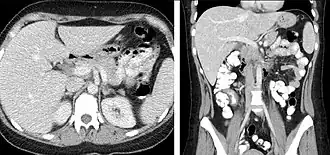

-

FIGURE 2. Contrast enhanced CT demonstrating parenchymal enhancement of the intra-abdominal organs in the portal venous phase (axial left, coronal reformat right).